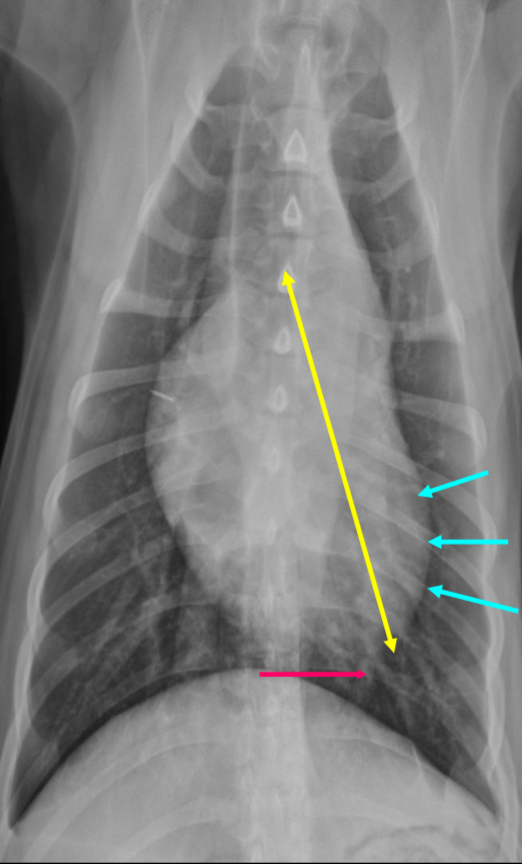

3 features of LVE VD

-elongation of cardiac silhouette

-deviation of apex to the left

-bulge at 3-5 o’clock

What part of the heart is enlarged?

LVE

RAE feature on VD

Bulge at 9-11 o’clock region ± RVE bulge

RAE

2 features of RVE on VD

-bulge 5-9 o’clock

-reverse D

What part of the heart is enlarged

RVE